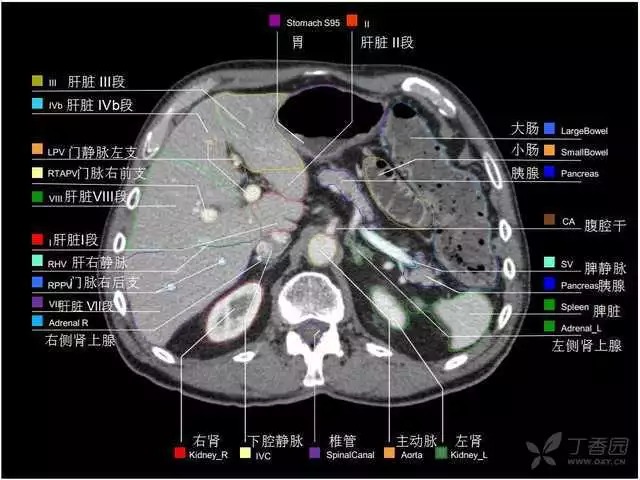

腹部肝脏高清CT断层的图谱

全腹部高清CT图谱,淋巴结彩色图谱,血管解剖图谱大汇总!

超声肝脏分叶及分段

肝脏分段和基本解剖学标志